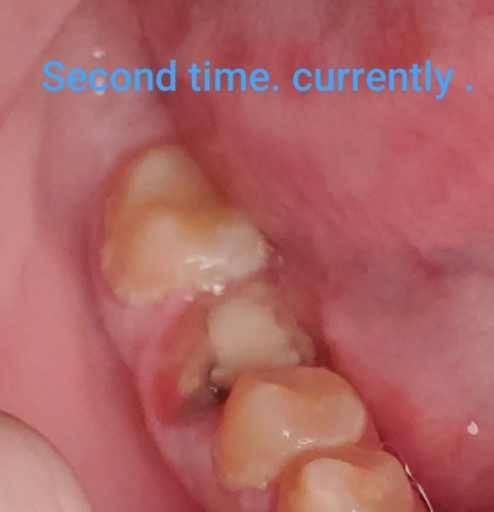

I have a crack in the lower back of my temp crown and light blood is coming from their

I have a crack in the lower back of my temp crown and light blood is coming from their It has happened twice now, yesterday and today There is also a slight pain when drinking water and both time the bleeding was just after I drank water I can’t see my dentist until next week I have this temp crown for 3 years now and have to wait another year to get a permanent one due to financial problems and nerve has also been removed in this particular tooth due to abscess in the past HELP PLEASE!!!!! Is it serious? What’s happening? Why is their blood?